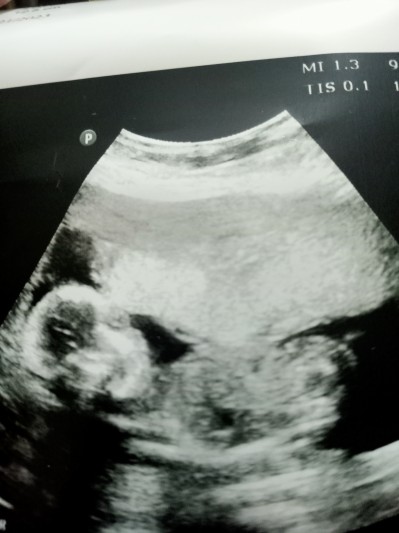

bugün doktora gittim erkeğe benziyor dedi bir çıkıntı olduğunu söyledi Kordon'da olabilir dedi. Sizce değişirmi 18 haftalık olduk.

Kordon olabilir demişse kız olma ihtimali var %50 kız %50 erkek

Banada çıkıntı var dedi 13 haftada iki hafta oldu tekrar gidicem netleştirmeye kordon demedi ama bakalım bu defa ne diyecek